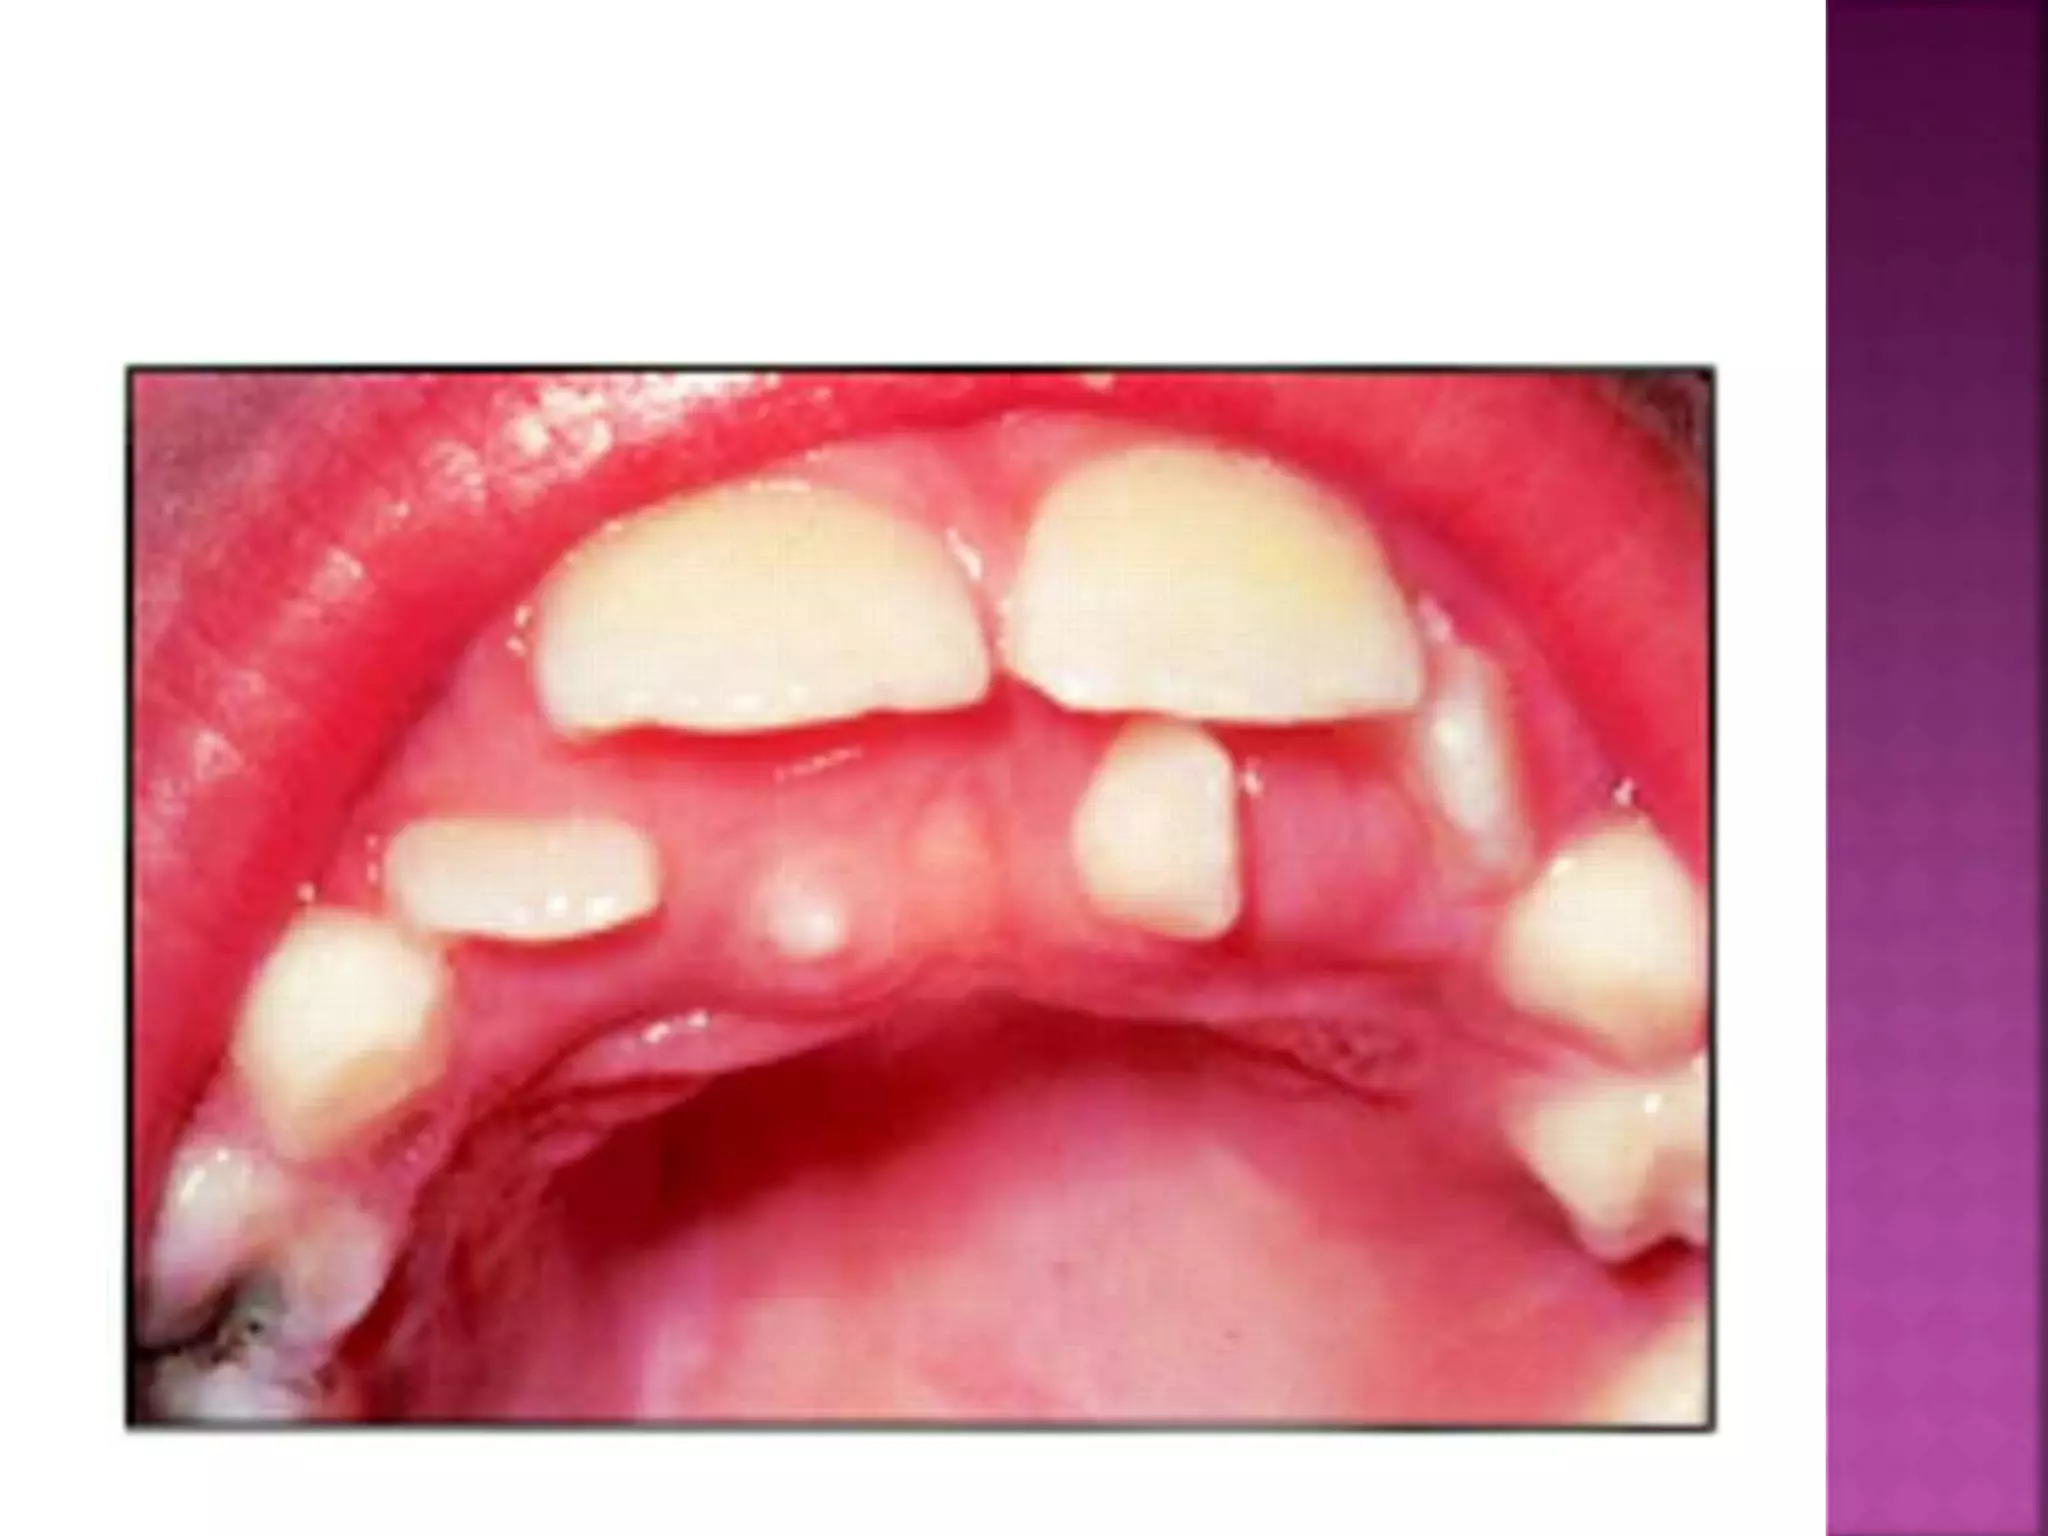

The deciduous teeth are more or less vertical in the

alveolus, so that when occlude, there is little

dislodging force ..